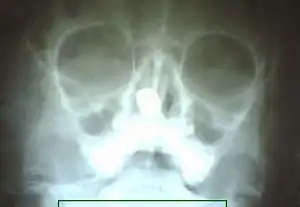

X-ray of paranasal sinuses showing rhinolith